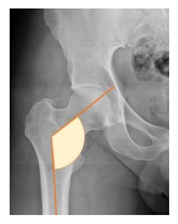

| Lateral center-edge angle (lcea) | The angle measured between two lines drawn from the center of the best fit circle for the inferior and medial margins femoral head, one running vertically along the longitudinal axis of the pelvis and the other to the lateral acetabular rim [23,24] | 25–39° | ![]() |